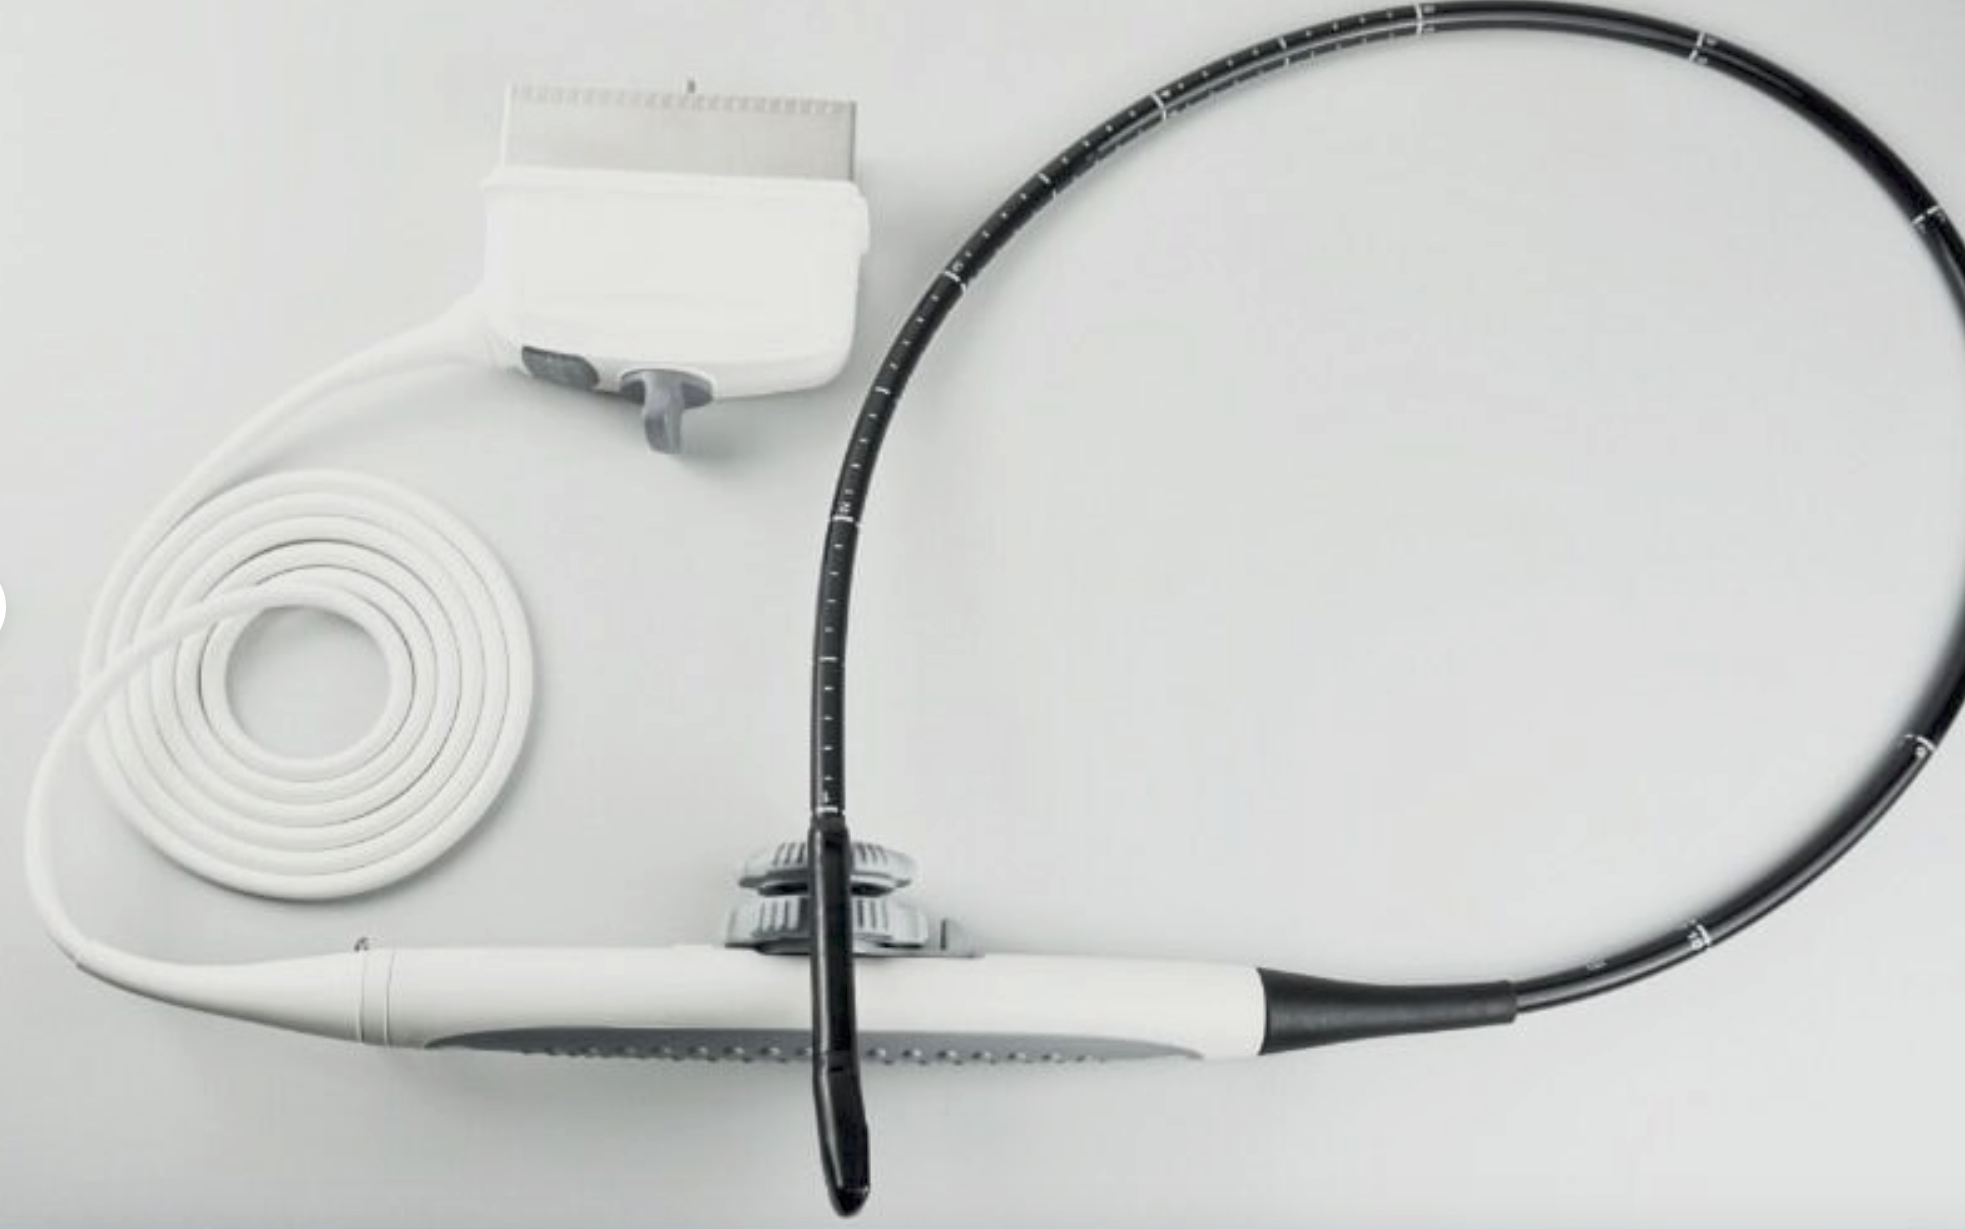

DIAGNOSTIC ULTRASOUND MACHINES FOR SALE

Ultrasound Scanner machine Rectal Probe 3D Laptop Machine Digital Veterinary AA 190891879431

Sale price$ 1,866.31

Regular price$ 2,275.99